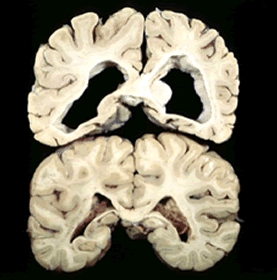

Malattia di Huntington: biomarcatori utili per diagnosi precoce della malattia

La malattia di Huntington è una malattia ereditaria che porta  alcune cellule nervose del cervello alla  morte, con conseguente disfunzione motoria, declino cognitivo e sintomi psichiatrici. Essa è l’unica grande malattia neurodegenerativa in cui la causa è nota con certezza: una mutazione genetica che produce un cambiamento di una proteina che è tossica per i neuroni.